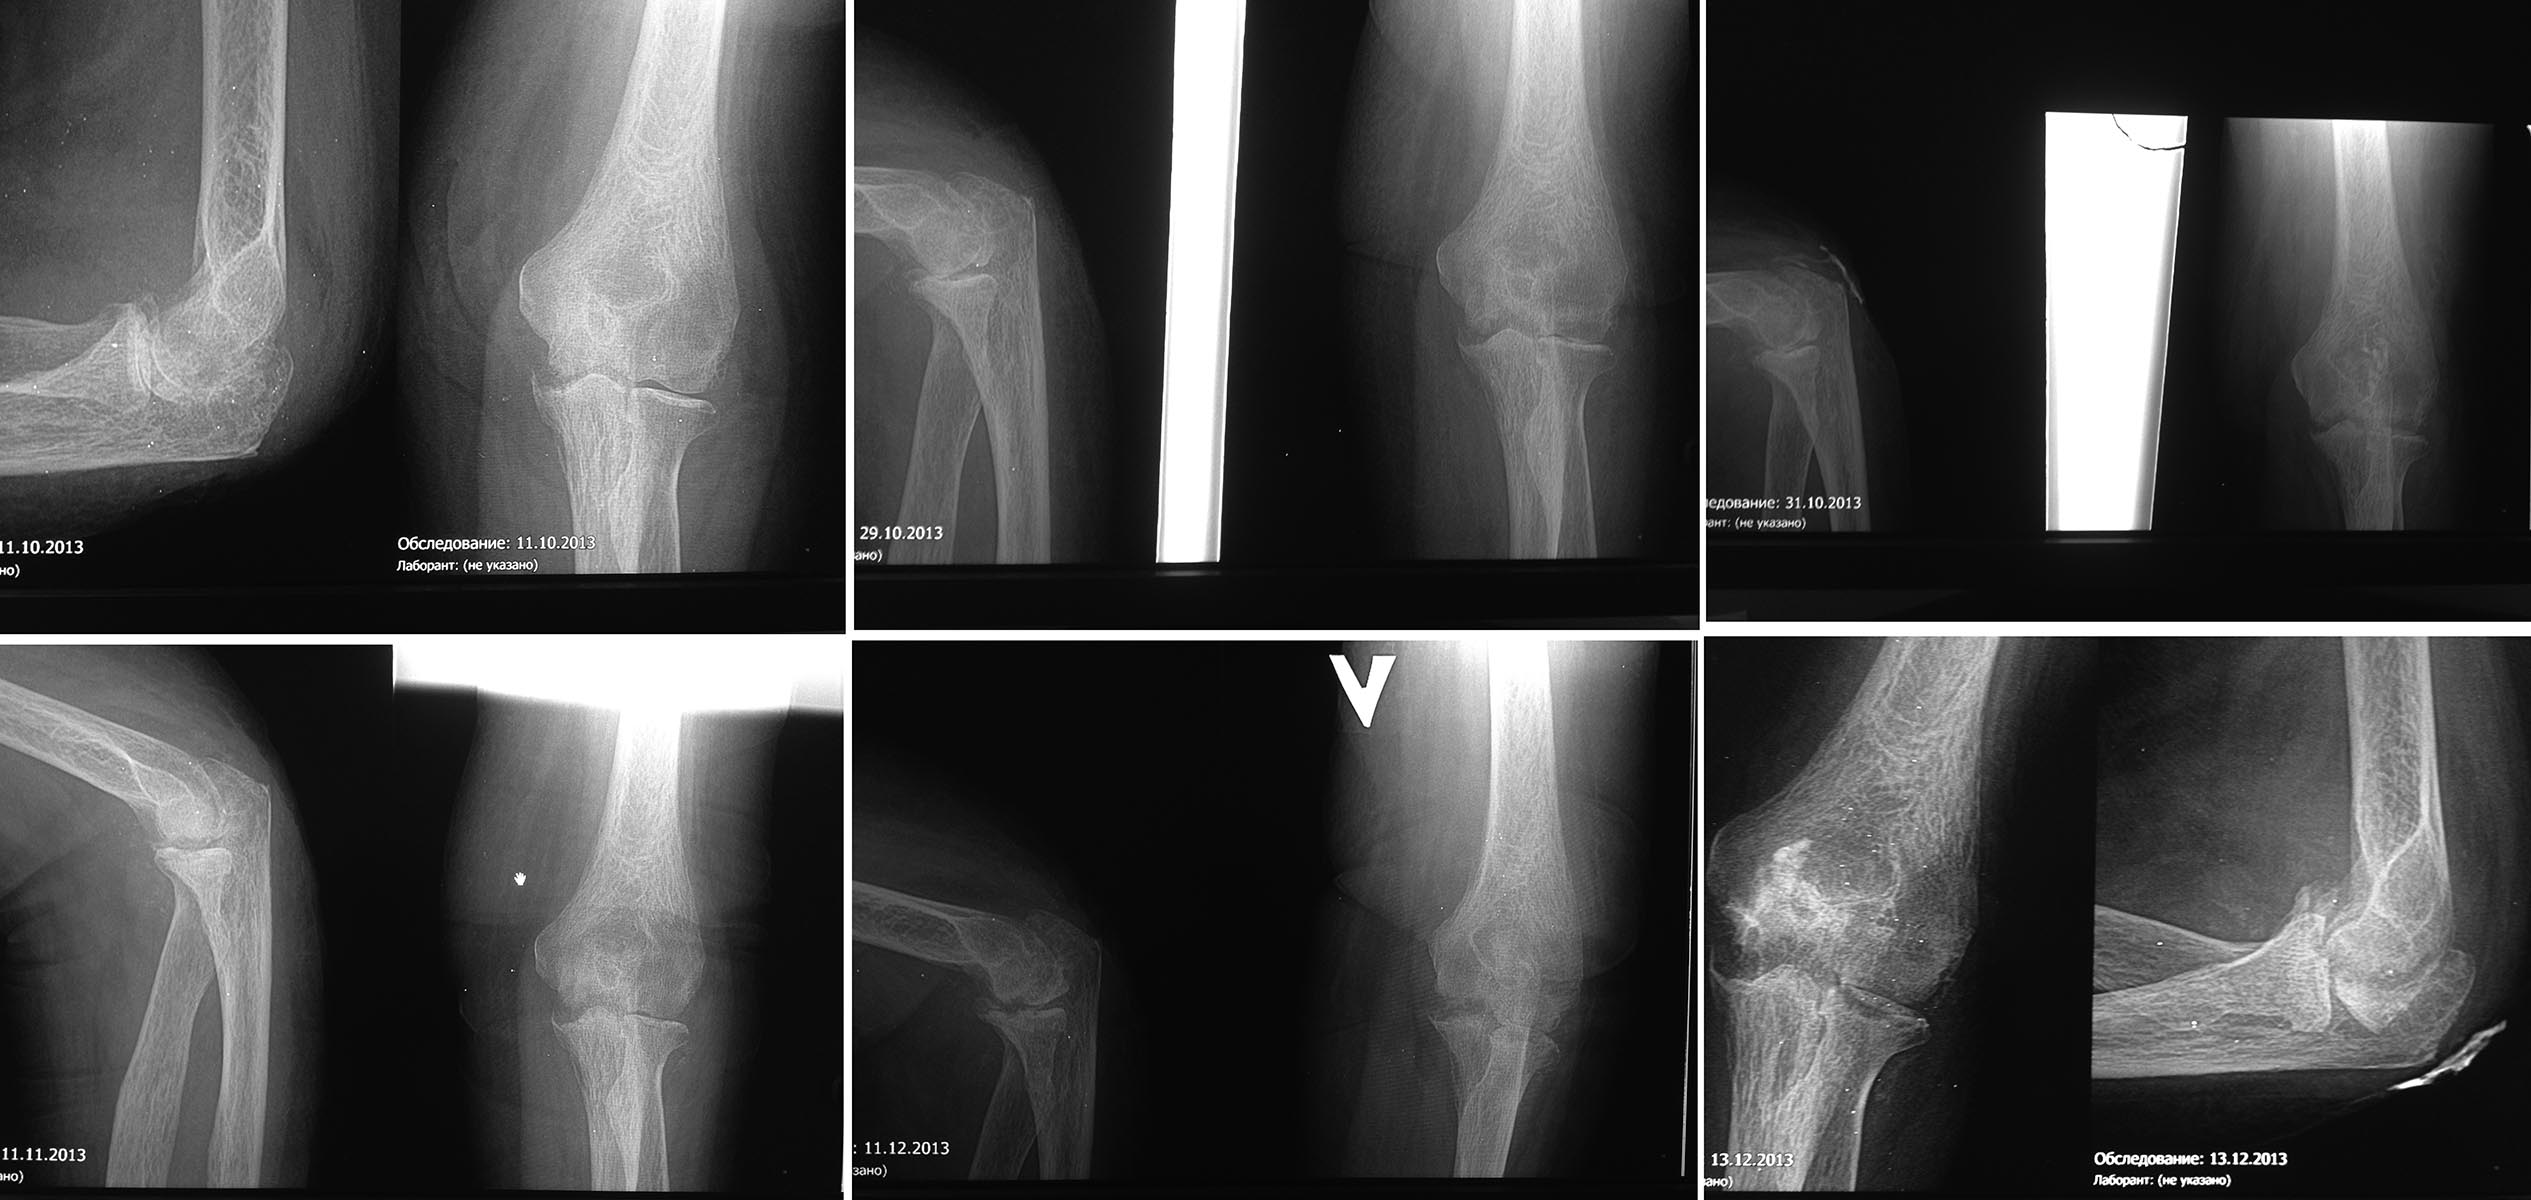

Прошу вашей помощи в определении тактики лечения пациентки с остеомиелитом костей локтевого сустава. Добрый день, уважаемые коллеги! Прошу вашей помощи в определении тактики лечения пациентки. Больная 64-х лет, страдает Ревматоидным артритом, получает гормональную терапию – т. Преднизолон 2т утром (ежедневно). В июне 2013, в нашей ЦРБ мной выполнена операция – Иссечение бурсы локтевого отростка. П/о период б/о. После выписки из отделения лечилась амбулаторно, выполнялись пункции области п/о рубца в связи со скоплением серозной жидкости. Спустя 2 месяца появились отёк, гиперемия, подкожная флюктуация в проекции п/о рубца, болевой синдром в локтевом суставе при движении. Обратилась на прием к хирургу, после пункции выявлено гнойное содержимое. Назначена антибактериальная терапия, выполнялись повторные пункции. В динамике открылся свищевой ход в проекции п/о рубца. После отсутствия положительной динамики выполнена R-графия локтевого сустава, выявлена деструкция костной ткани.

В ноябре 2013, с диагнозом Остеомиелит медиального надмыщелка плечевой кости и локтевого отростка слева направлена на стац. лечение в ХО. При осмотре выявлен болевой синдром, ограничение движений в локтевом суставе, а также костная крепитация при нагрузке на связочный аппарат. Выполнялась фистулография – контраст вокруг капсулы на ограниченном участке, в сустав не проникает.

Консультирована по телефону с зав. травм. отд. обл. б-цы – рекомендовано продолжить консервативную антибактериальную терапию до купирования гнойного отделяемого и закрытия свища. За время стац лечения купировано гнойное воспаление, свищ закрылся, сохранялось ограничение движений в локтевом суставе (незначительно увеличились), боль при движении. В удовлетворительном состоянии выписана на амбулаторное лечение. Через месяц рецидив заболевания. В декабре 2013 повторно госпитализирована в ХО. Из свища обильное гнойное отделяемое. Локтевой сустав фиксирован под углом 45о, движения качательные в пределах 5-10о. На рентгенограммах отрицательная динамика – деструктивные изменения суставных поверхностей костей локтевого сустава. Выполнялась фистулография – контраст проходит до локтевого отростка, в сустав не проникает. Проведена антибактериальная терапия, перевязки. За время стац лечения купировалось гнойное воспаление, свищ закрывался, сохранялось ограничение движений в локтевом суставе, боль при движении. Через 2-3 недели рецидив.

Выкладываю снимки, извиняюсь за качество.